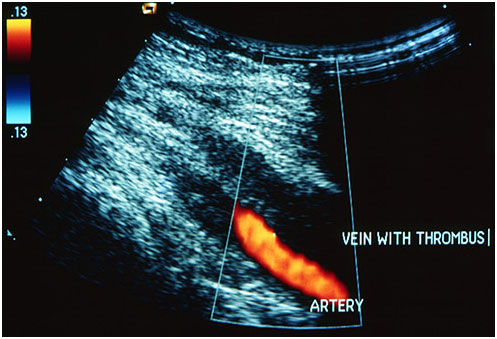

醫(yī)生會(huì)檢查你是否有DVT跡象。他可能會(huì)問你的病史,你正在服用的藥物,近親的醫(yī)療問題,以及那些可能增加你患病風(fēng)險(xiǎn)的因素。超聲波檢查是最常用的診斷方式。超聲波可以觀察血流并顯示血凝塊。你可能還需要其他的測試,比如一種叫做d-二聚體的血液測試。